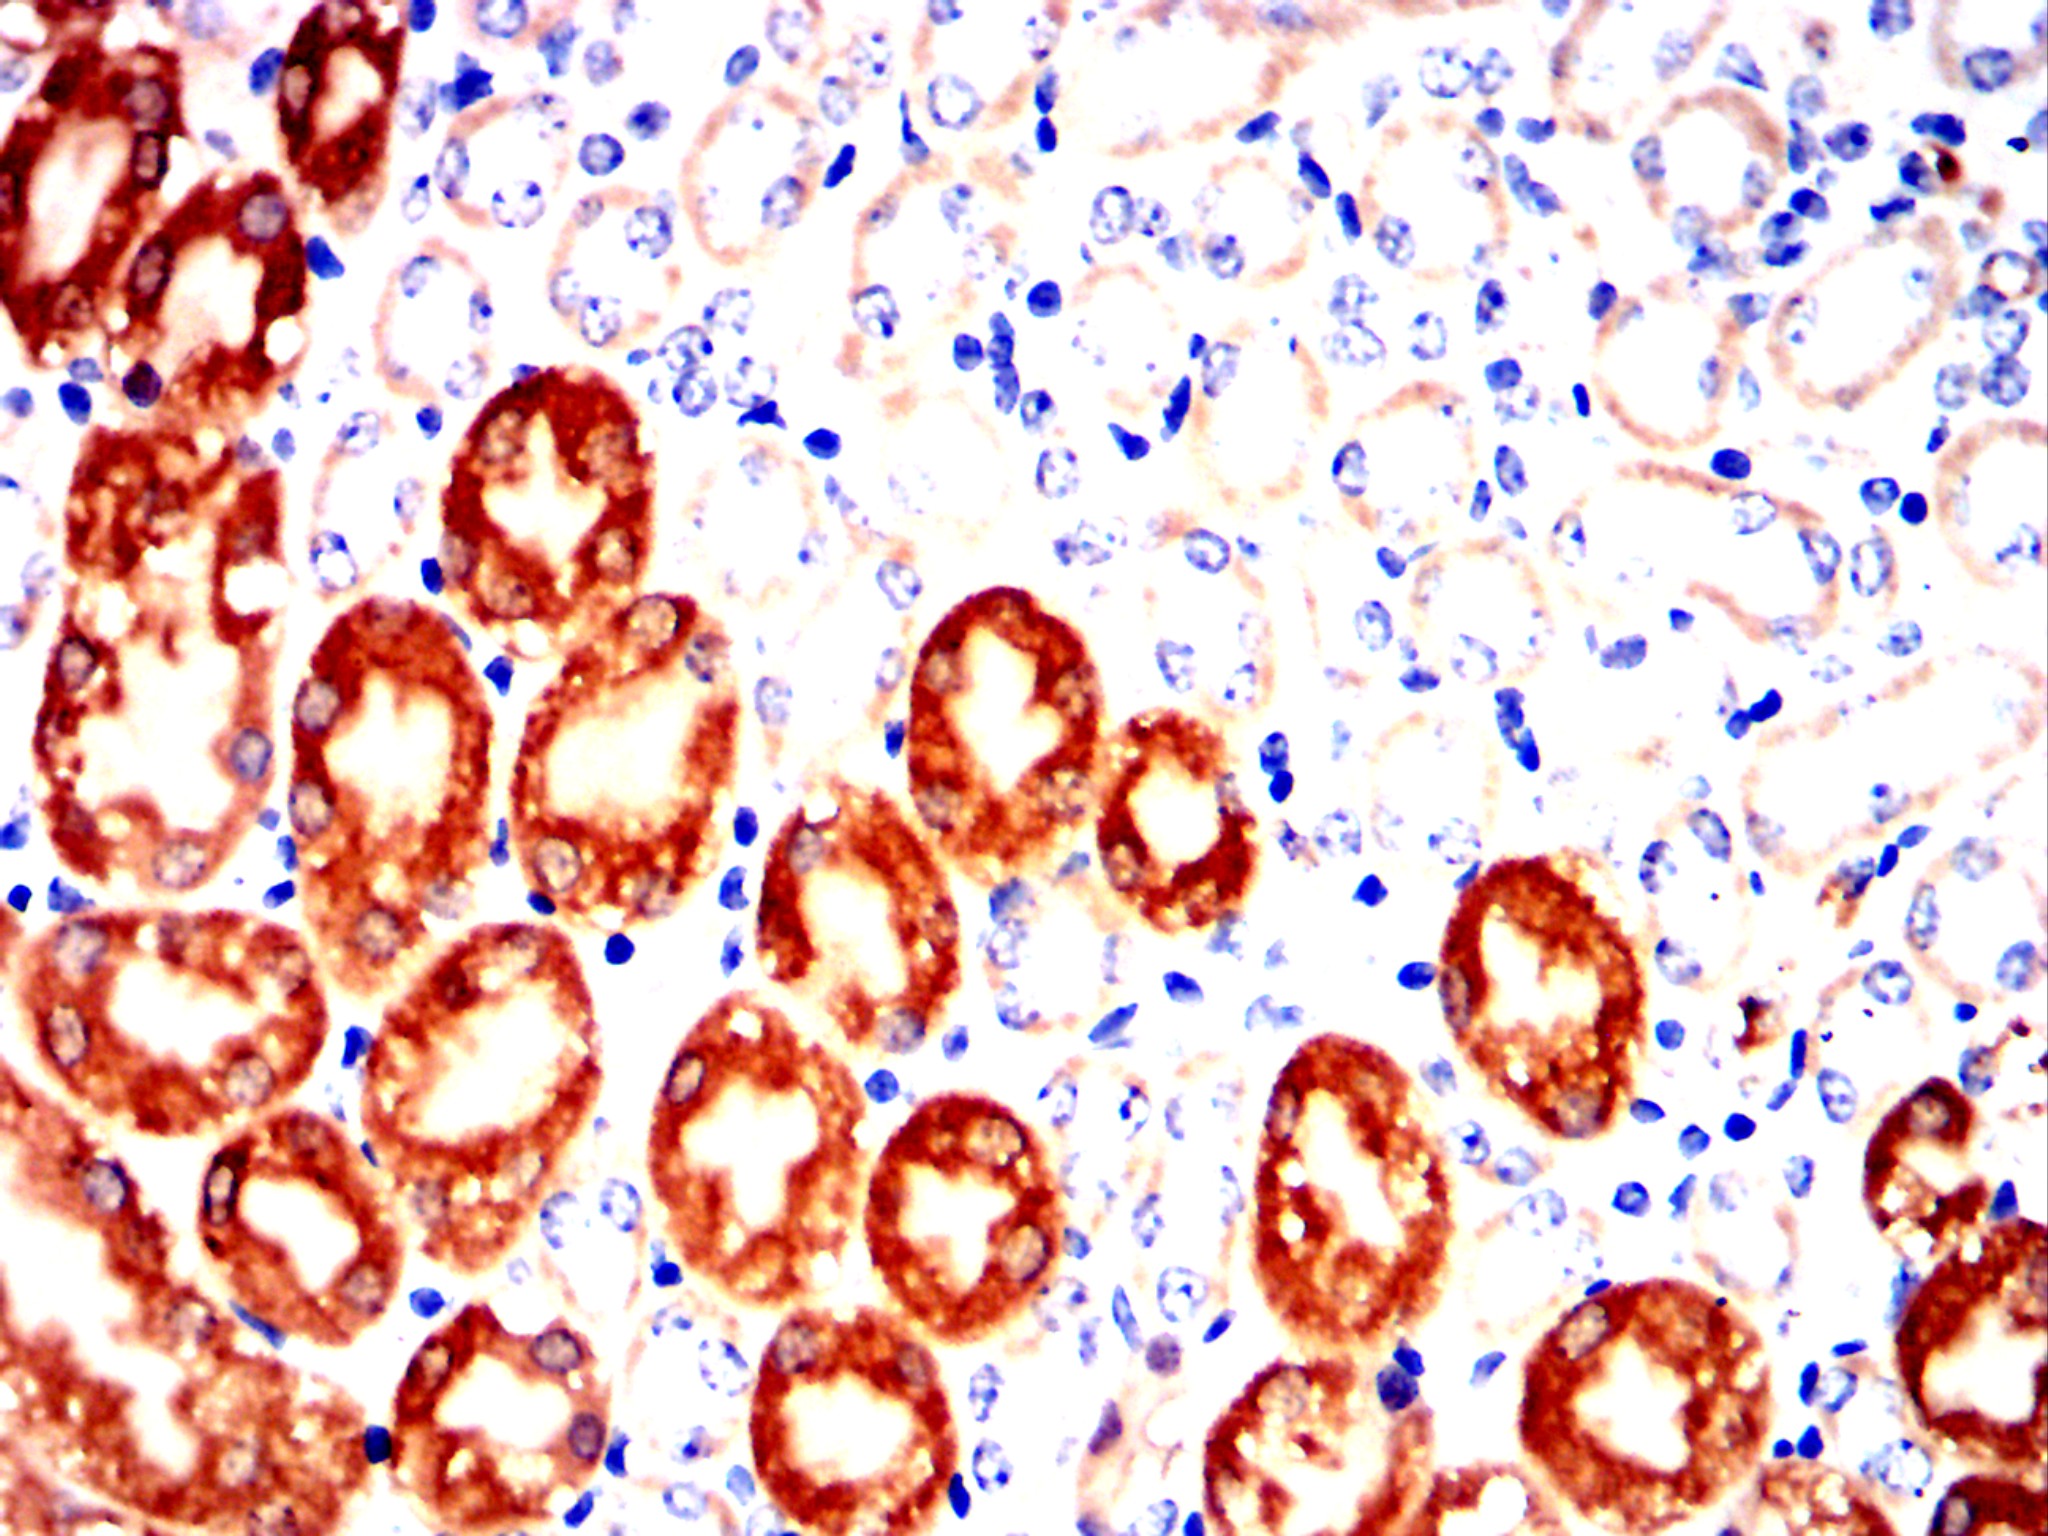

Immunohistochemical analysis of paraffin-embedded human pancreas tissues using SST mouse mAb with DAB staining.

Immunohistochemical analysis of paraffin-embedded Mouse kidney using SST mouse mAb with DAB staining.